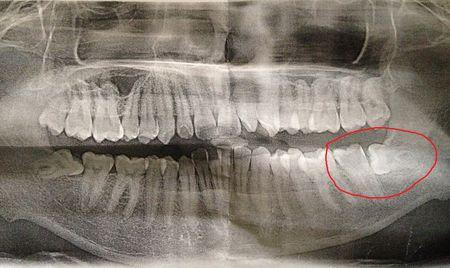

牙齿侧穿图片,根管侧穿图片

问:可能发生侧穿的龋齿是做治疗还是拔了?

根管侧穿图片

根管治疗侧穿图片